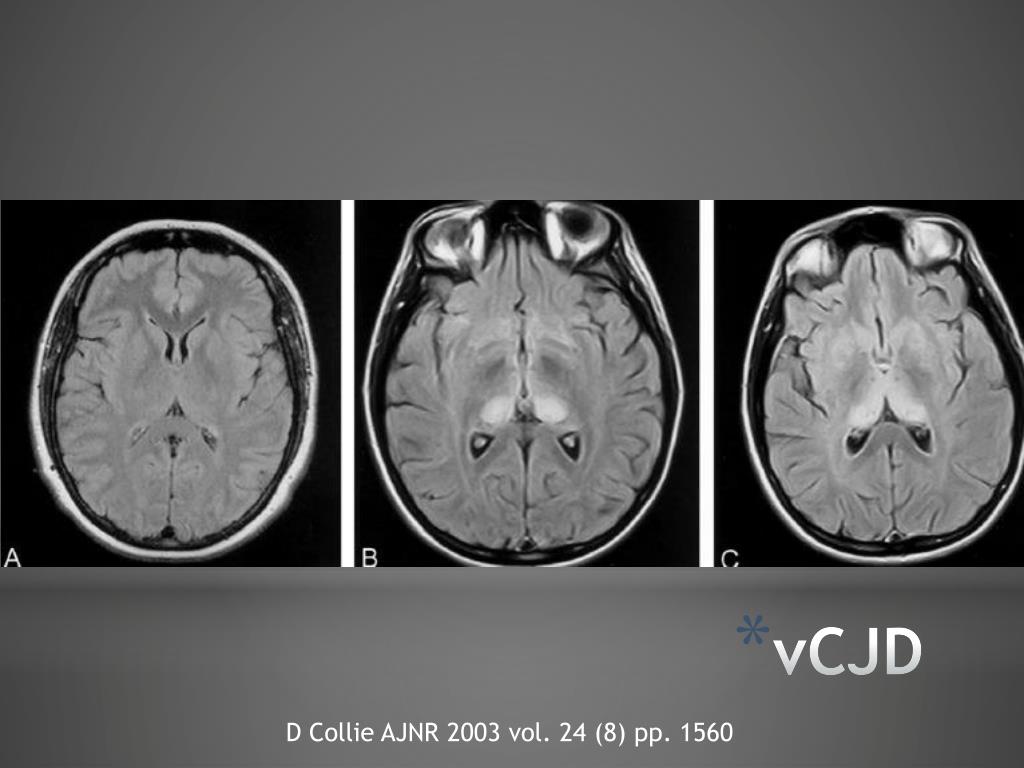

13. vCJD D Collie AJNR 2003 vol. 24 (8) pp. 1560

14. vCJD D Collie AJNR 2003 vol. 24 (8) pp. 1560